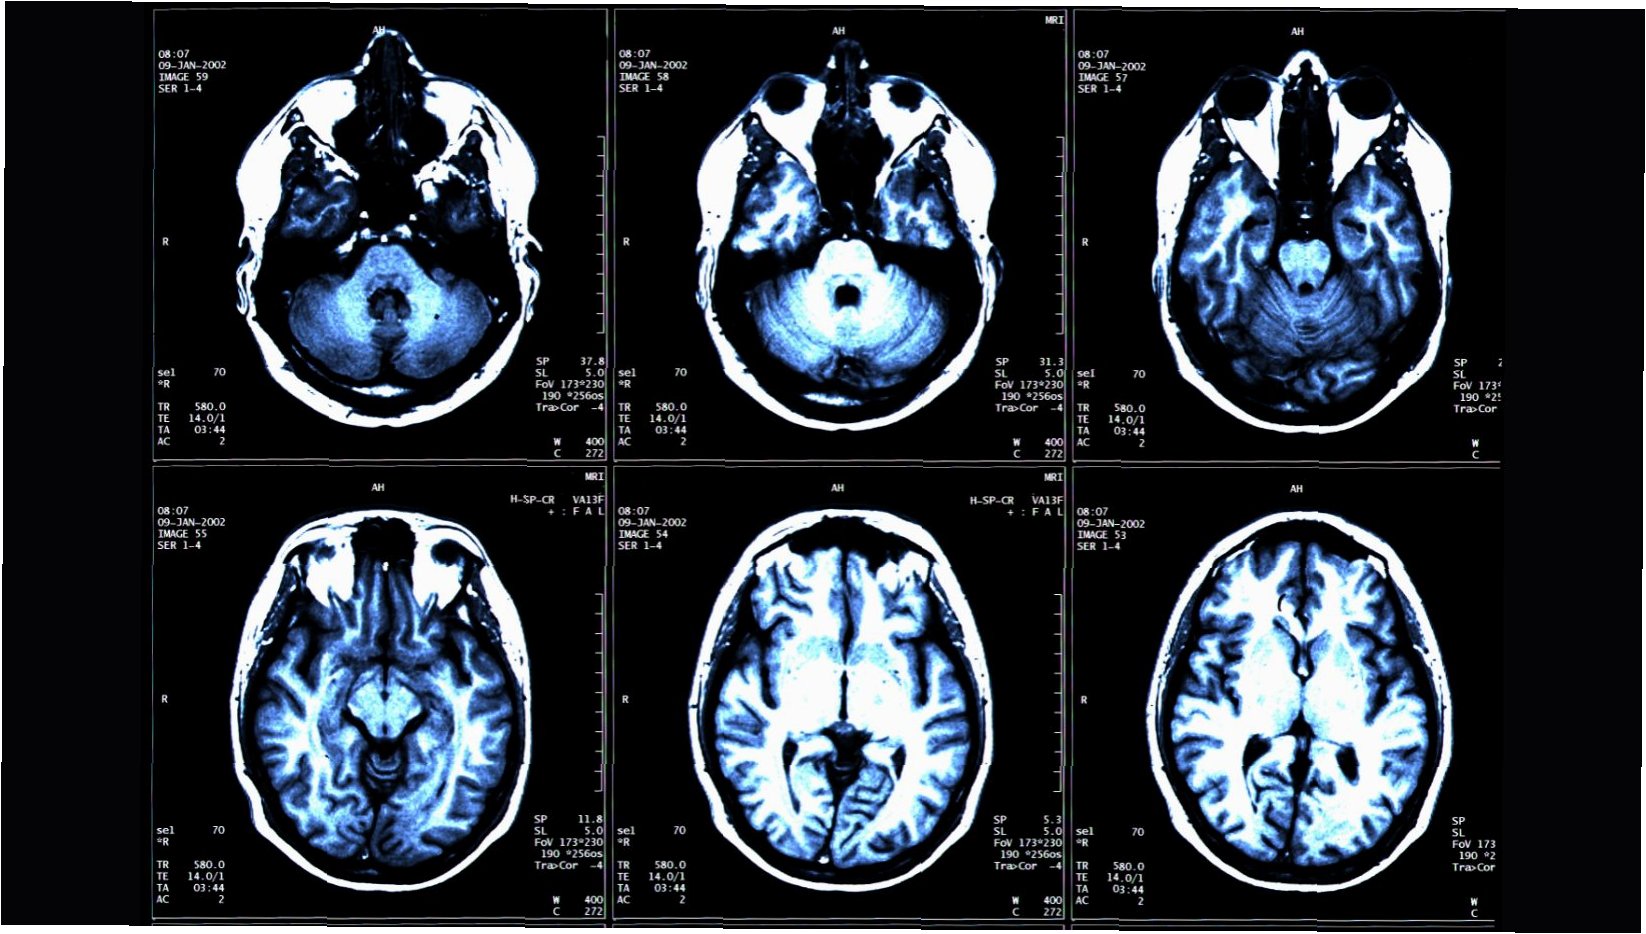

최근 연구에 따르면, 근육량이 많고 복부 지방이 적을수록 뇌 노화 속도가 늦춰지는 놀라운 결과가 밝혀졌습니다. 미국 워싱턴대 의대 연구팀은 1164명의 건강한 성인을 대상으로 전신 MRI를 촬영하여 근육량, 지방, 그리고 뇌 조직 간의 상관관계를 분석했습니다. 이 연구 결과는 오는 30일 미국 시카고에서 열리는 북미영상의학회 연례 학술대회(RSNA 2025)에서 발표될 예정입니다.